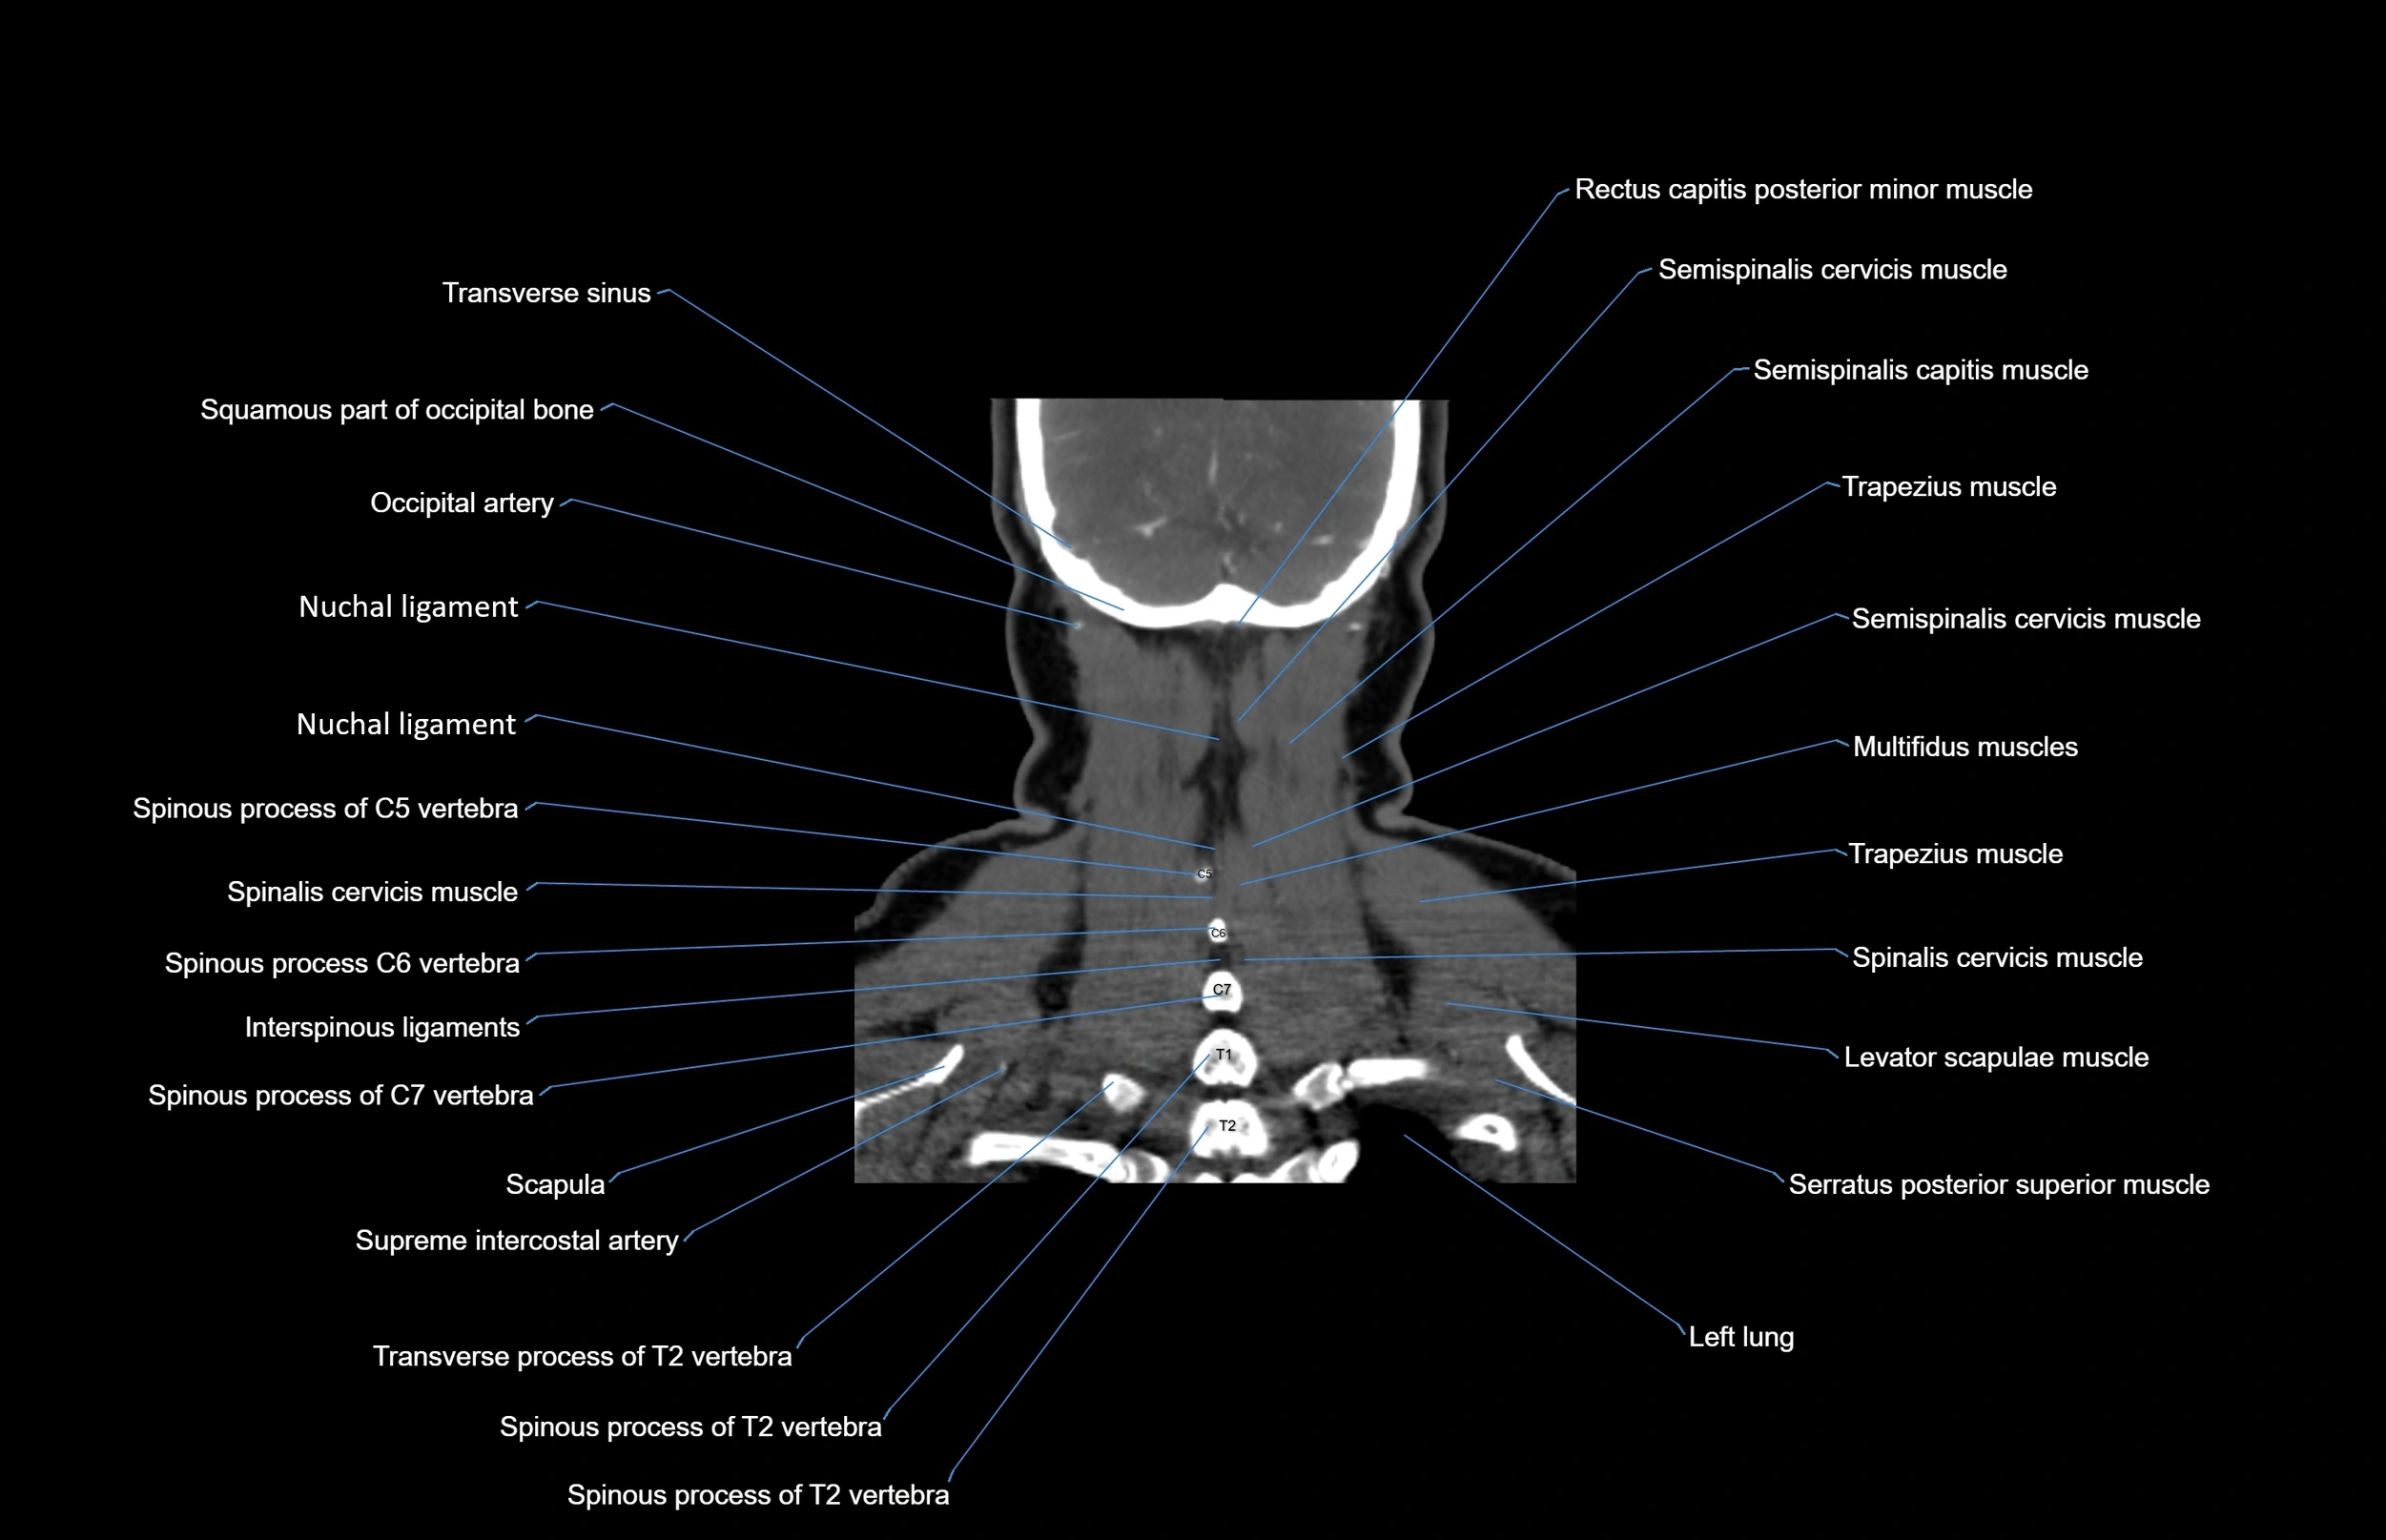

- Multifidus muscles

- Semispinalis capitis muscle

- Semispinalis cervicis muscle

- Spinalis cervicis muscle

- Spinous process of vertebra

- Trapezius muscle